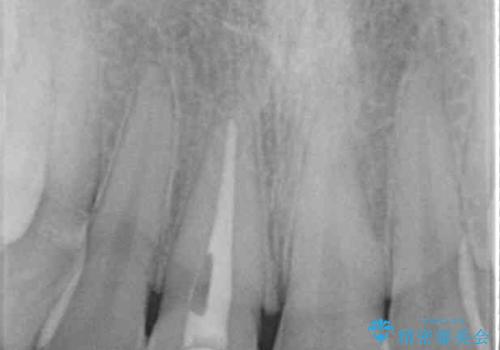

レントゲン写真より、歯根の炎症が認められなかったため、ファイバーコアによる土台築製後、オーダーメイドタイプのオールセラミッククラウンにて補綴することとしました。